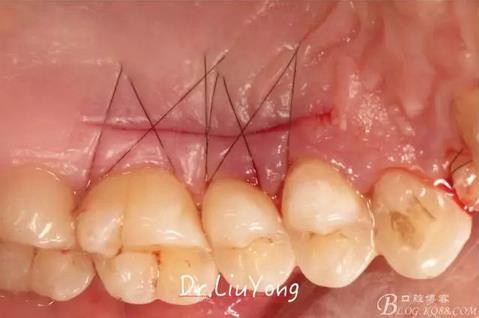

縫合關(guān)閉供瓣區(qū)域,如上圖